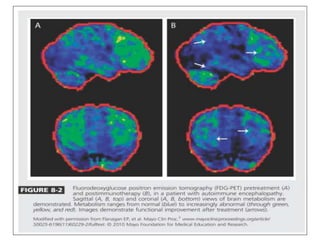

FUNCTIONAL IMAGING :

• Global hypometabolism is the most common feature

encountered in patients with autoimmune encephalopathies.

• However, focal hypometabolism can also be encountered.

• In instances where the patient has seizures, hypermetabolism

can occur.